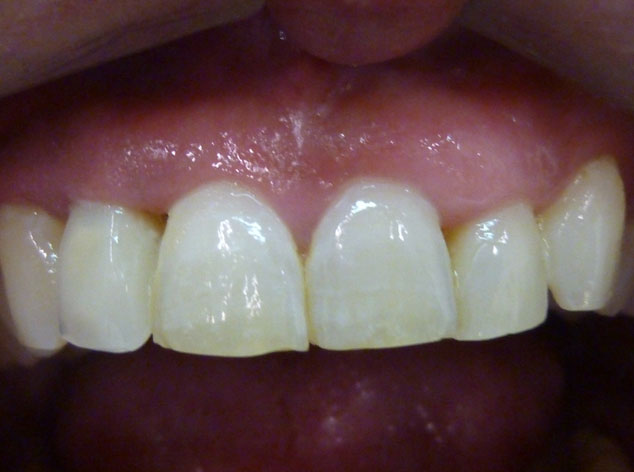

Es una técnica, pero sobre todo es una filosofía de trabajo. Ha sido descrita y registrada por nosotros y esta basada en un hecho sencillo, pierdes un diente o extraemos el diente enfermo y problemático, y en la misma sesión, el mismo día colocamos el diente nuevo con una mejora de la estética evidente.

All-at-once, te asegura mejor estética y función en una sesión, en un día, en contra de los 8 largos meses.

En estos casos han sido tratados con la filosofía de all-at-once, en la

misma sesión: